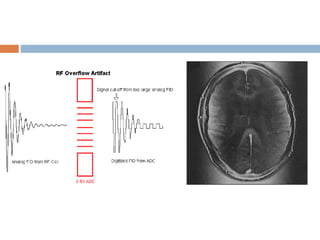

RF overflow artifact

 Non uniform, washed out appearance in an

image.

 Occurs when the signal received from the patient

is too intense to be digitized by analog to digital

converter.

 Auto prescanning usually adjusts the receiver

gain.

 Post processing methods also existing but may

be time consuming.

• 33.

RF overflow artifact Non uniform, washed out appearance in an image.  Occurs when the signal received from the patient is too intense to be digitized by analog to digital converter.  Auto prescanning usually adjusts the receiver gain.  Post processing methods also existing but may be time consuming.